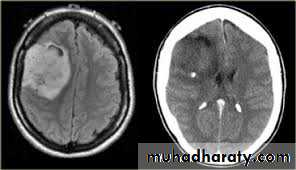

Secondary metastasis

Old age group above 50 Y , any lesion within the cerebellar hemisphere it is secondary metastasis unless proven otherwise F. from breast CA M. from bronchogenic CA .

Appear as nodular single or multiple lesion hypo dense or hyper dense .

Surrounded by per focal edema

Enhanced as solid or ring pattern of enhancement .

CT Scane